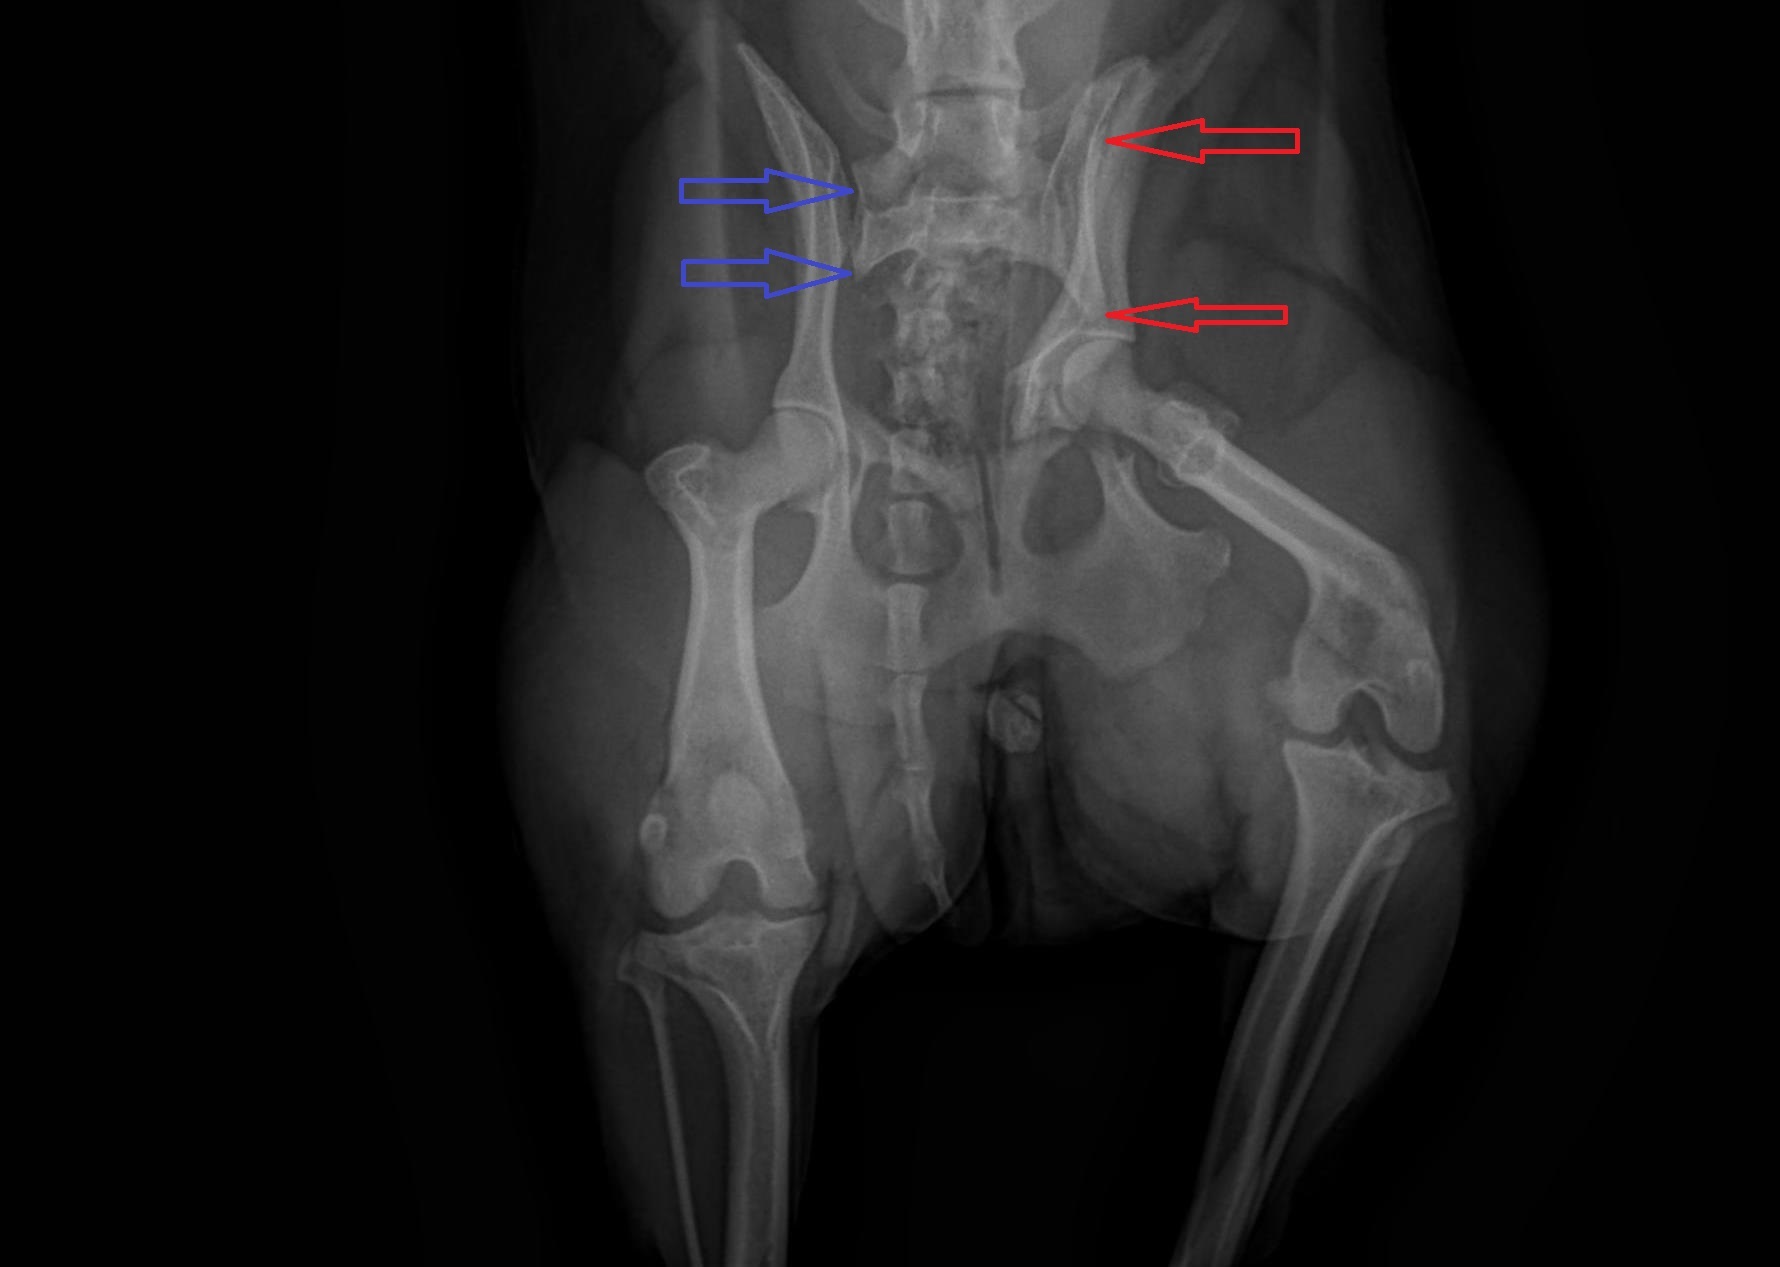

Vets are keeping her in for another 24 hours, they have said that she's comfortable and. Cat with broken pelvis after hit by car. Hit by a car, broken pelvis the man that rescues dogs facebook.

After 6 weeks cage rest and one failed attempt to pop the hip back, my vet. Sophie, a nine year old cat who suffered a broken pelvis after being hit by a car. She has a fractured pelvis and her tail is.

With a fractured hip (separated from the pelvis by a good distance), the vet said she. She arrived back home tuesday afternoon, we got her to a vet that night because her leg looked broken. Our cat joe, who has featured on these forums before, was hit by a car this morning.